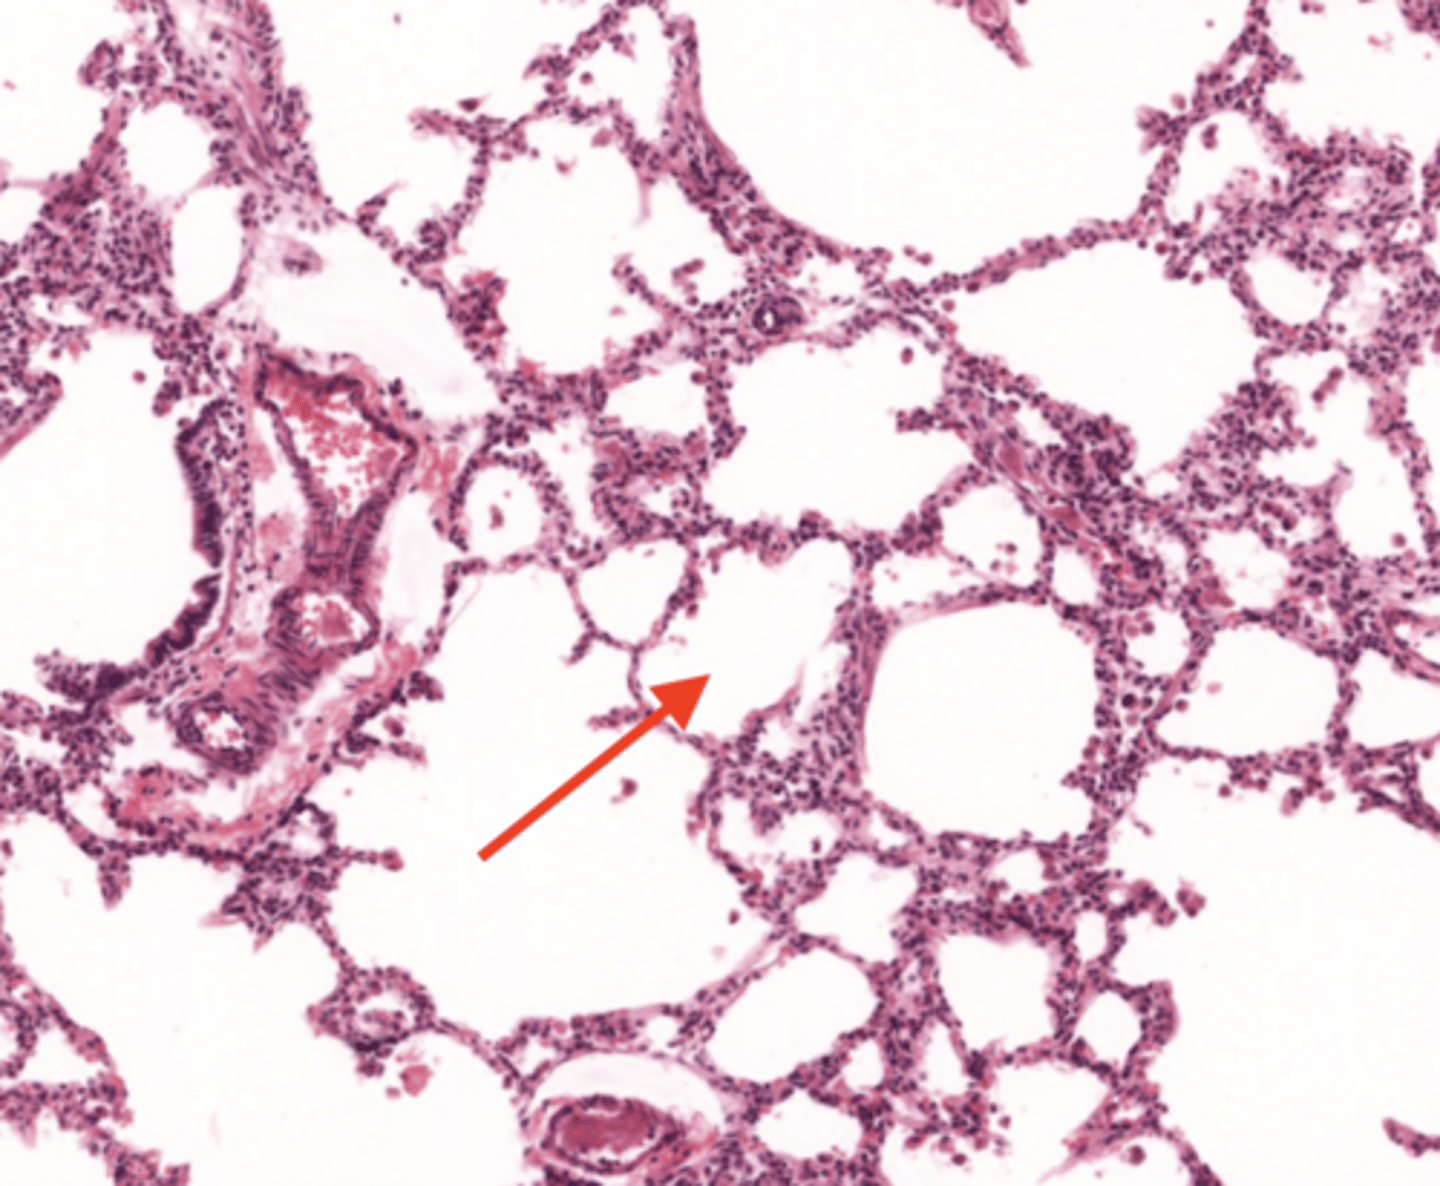

lung (normal)

alveolus (normal)